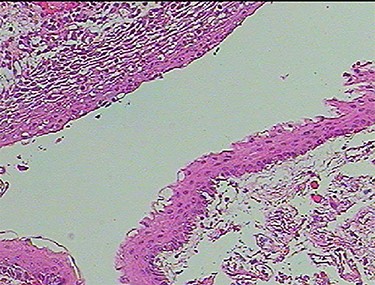

A 3-year-old male, who suffered from a sudden, tonic–clonic seizure, followed by a short period of unconsciousness, was instantly transported to Children’s Hospital 2. The patient’s medical history was normal. No neurological deficits were detected during the clinical assessment, and laboratory tests and electroencephalography were within acceptable ranges. The clinician performed a brain magnetic resonance imaging (MRI) scan, with contrast agent. No lesions were recognized in the supratentorial structures. A clear boundary cystic mass (27 × 25 × 26 mm3) was located in the medulla oblongata, without perilesional vasogenic edema. Hydrocephalus was not observed. The signal intensity of the mass was low on the sagittal T1-weighted image (Fig. 1) and high on the axial T2-weighted image (Fig. 2). On coronal fluid-attenuated inversion recovery imaging, the mass was isointense relative to the parenchyma, but the intensity was higher than that of cerebrospinal fluid (CSF, Fig. 3). On susceptibility-weighted imaging, no indicators of hemorrhage or ossification were observed within the mass. The mass was partially hyperintense on diffusion-weighted imaging (DWI) and slightly hypointense on the apparent diffusion coefficient (ADC) map. The mean ADC values of the parenchyma, mass and CSF were 0.71, 1.3 and 1.59 × 10−3 mm2/s, respectively (Fig. 4). On T1-weighted imaging, with contrast enhancement, the thin wall of the mass was very slightly enhanced, and we observed a tiny nodule inside the mass that was strongly enhanced (Fig. 5). With a provisional diagnosis of pilocytic astrocytoma, the patient underwent surgery to completely eradicate the tumor. Eventually, the histopathological result revealed a typical EC (Fig. 6). The postoperative period was uneventful, and the patient was discharged after 2 weeks.

Photomicrograph of the biopsy specimen, showing that the tissue sample presents a cystic structure, packed with laminated keratin. Multilayered squamous epithelia are stratified on the cyst wall. No skin appendages are observed (hematoxylin and eosin, ×40).

Histopathologically, the ECs are filled with protein, keratin and cholesterol. The cyst wall is typically covered with stratified, squamous epithelia, with the outward backing of collagen [3–8]. The appearance on MRI is heavily dependent on the chemical architecture of these intracystic components. The hypointensity observed on T1-weighted images is associated with the crystalline cholesterol pattern, whereas the hyperintensity on T2-weighted images is induced by the keratinaceous element. Occasionally, ECs appear hyperintense on T1-weighted images and hypointense on T2-weighted images, and these are referred to as white ECs [8, 9]. This specific appearance is caused by unusually high proteinaceous concentrations in the cyst. Typically, ECs do not absorb contrast agent vividly. Approximately 35% of ECs are estimated to enhance slightly and peripherally [9]. DWI is the most useful weapon that can be deployed to recognize ECs. When contrasted with the CSF, because of the superior keratinaceous and proteinaceous concentrations and the relatively little aqueous content, ECs generally appear considerably hyperintense on DWI and hypointense on ADC [9, 10].